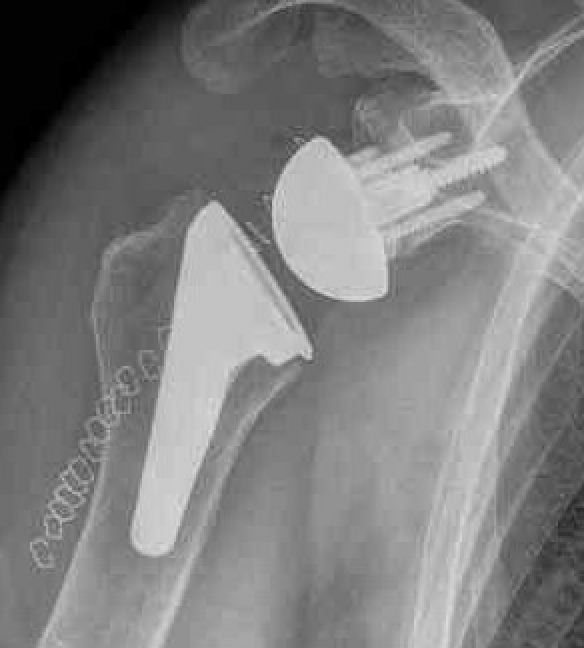

Reverse shoulder arthroplasty

Reverse

- socket in proximal humerus

- ball in glenoid

- center of rotation shifted medially and distally

- allows deltoid to apply compressive force and stabilize joint in absence of rotator cuff

Paul Grammont in 1985

- humeral component concave

- glenoid component / glenospere convex

- glenoid component uncemented with peripheral screws and central plug

- center of rotation shifted medially to glenosphere with humerus distal